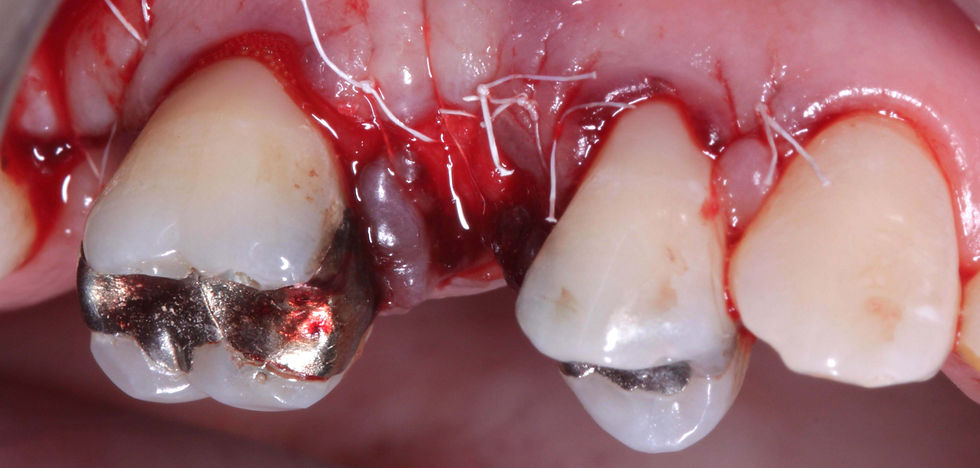

Initial clinical images of the crown on the 1.5.

First surgical step: an intrasulcular flap is raised and the root fracture is exposed after removing the crown.

At the removal of the fractured root, the bone defect is evident.

Tension-free secondary wound closure with PTFE sutures. Sutures are removed after 2 weeks